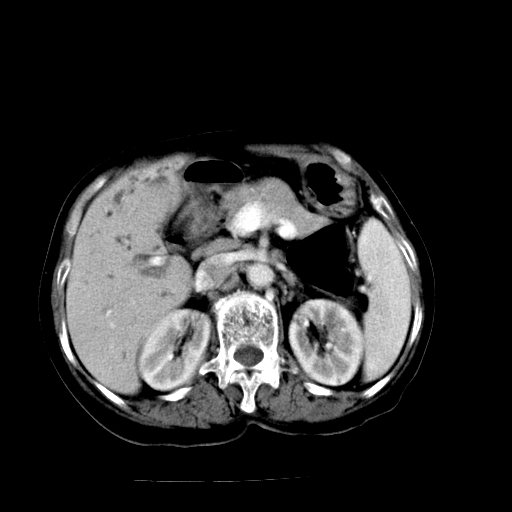

以下是引用卜一在2009-4-7 5:06:00的发言:[br]左右肝内胆管结石伴扩张合并胆系感染;不除外胆管细胞癌可能。支持! [br] [br]

以下是引用随光逐影在2009-4-7 8:21:00的发言:[br]肝内外胆管多发性结石并肝内外胆管扩张;胆系感染。